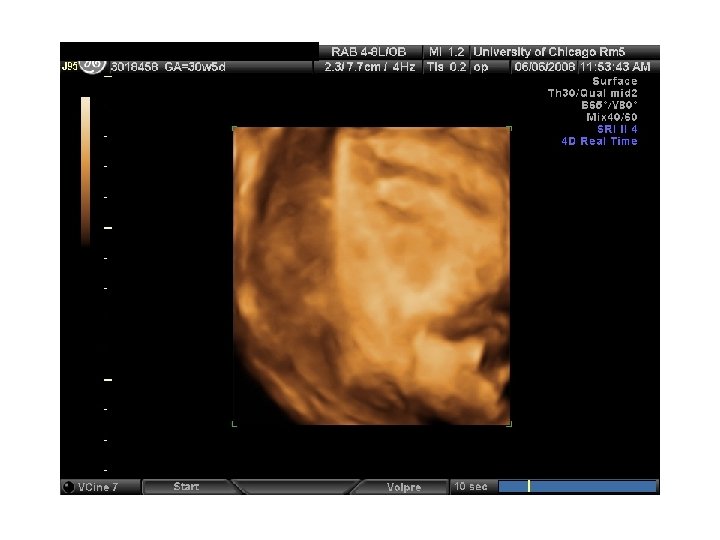

QUIZ What is Your Diagnosis? Case: Patient J. F. 30 years old, at 32 week gestation. Presented with the following pictures.

Answer: a) Trisomy 21 b) Non-immune Hydops c) Paravo virus Infection